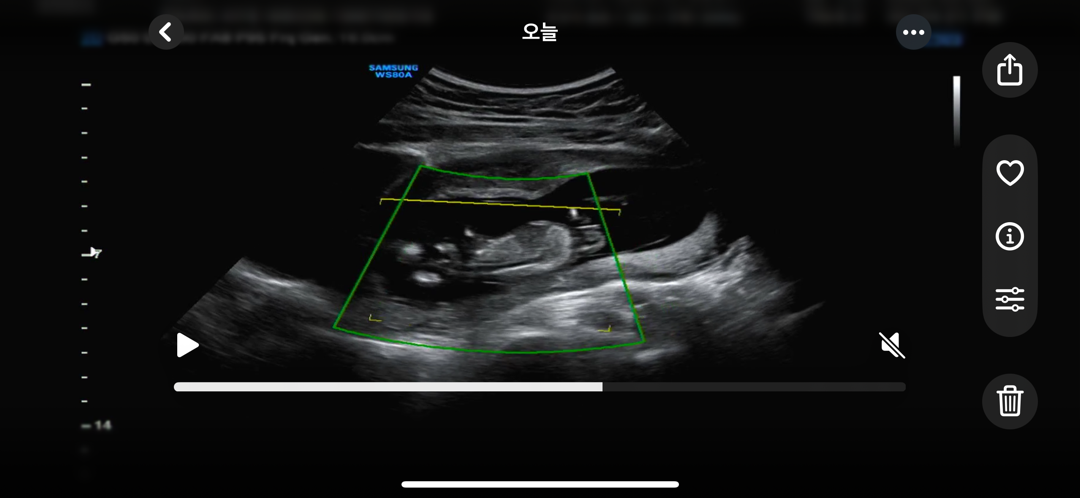

성별보이시는분 있나용?

13주입니당